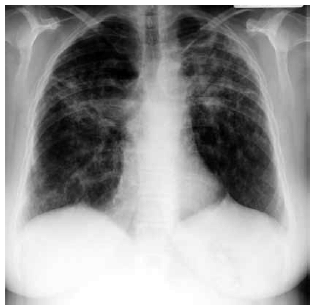

Mulher de 59 anos de idade relata quadro de fadiga, tosse seca e dispneia aos esforços há 1 ano. Nega antecedentes mórbidos, etilismo ou tabagismo. Ao exame físico: PA: 130 x 80 mmHg, FC: 88 bpm; FR: 20 ipm, SatO2: 94% e T: 38 ºC. cardiopulmonar: NDN. Exames séricos: creatinina: 1,1 mg/dL, glicemia: 82 mg/dL, cálcio 11,5 mg/dL (normal: 9 a 10,5), fósforo: 4,7 mg/dL (normal: 3,0 a 4,5), hormônio da paratireoide < 10 pg/mL (normal: 10 a 65) e 1,25-dihidroxivitamina D elevada. Teste cutâneo de tuberculina (PPD) é normal. A radiografia de tórax realizada é mostrada a seguir.